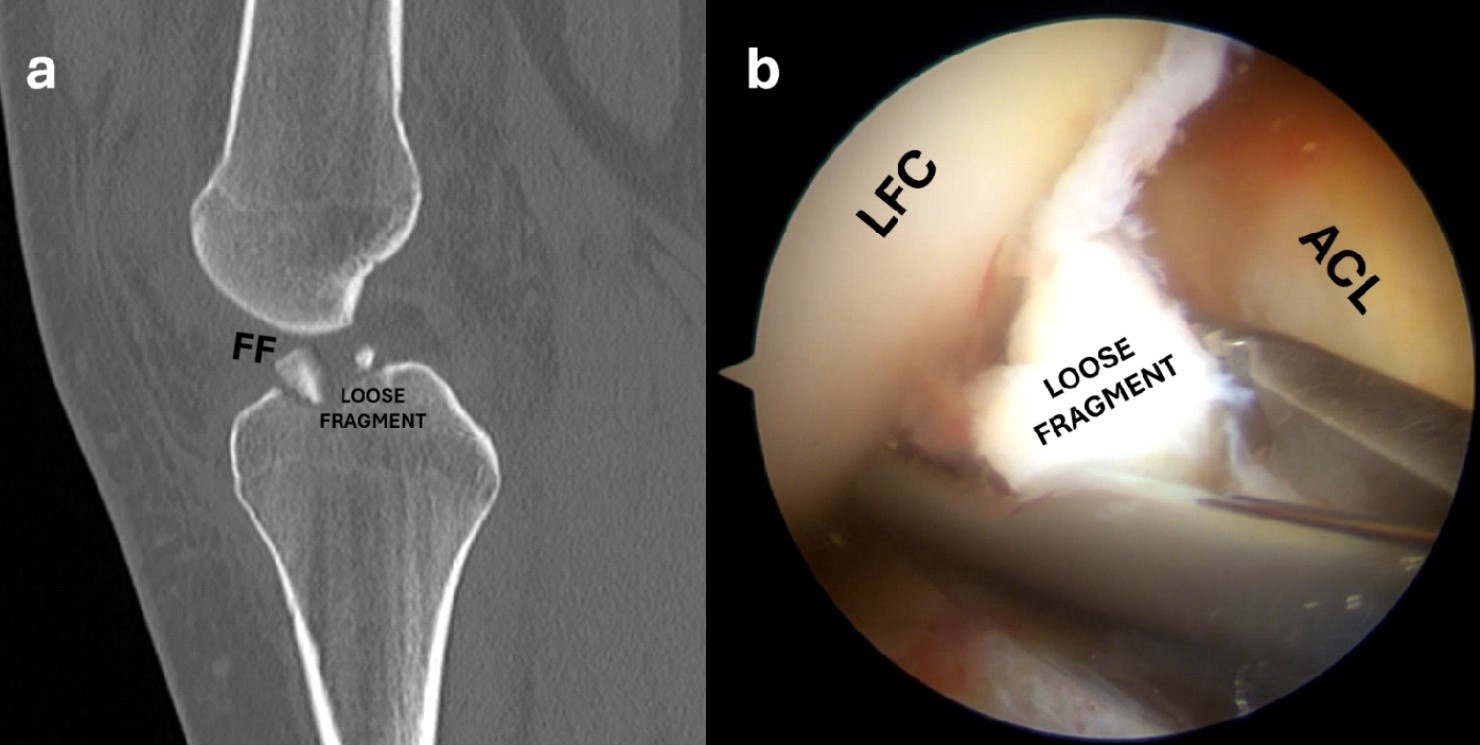

When enough visibility is obtained, the intraarticular hematoma is aspirated using a shaver through the anteromedial portal. During this stage, the ligamentum mucosum and part of the infrapatellar fat pad are resected to allow adequate visualization. After the hematoma has been evacuated, it is possible to inspect the joint for any other intra-articular lesions that should be addressed (Figure 2b, c). Care should be taken to check the condition and integrity of the anterior cruciate ligament (ACL) and the status of the articular cartilage and menisci, especially the anterior root of the lateral meniscus that could be avulsed with the spine. In this case, the anterior root of the lateral meniscus could displace the fracture fragment laterally and proximally (Figure 3). The fragment and its bony bed should be gently freed from hematoma and fibrous tissue to allow the study of the fracture pattern, keeping in mind the preoperative radiological exams. If the fracture is comminuted, small fragments (1-2 mm) should be removed to avoid producing loose bodies (Figure 4).

Figure 4. Sagittal CT scan showing a displaced and multifragmentary anterior eminence fracture with a loose fragment (a); the arthroscopic view shows a small loose fragment which is removed with a grasper (b).

LFC, lateral femoral condyle; ACL, anterior cruciate ligament.